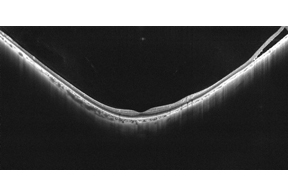

Canon OCT-S1で、痛みなく短時間で

目の奥を詳しく調べることができます